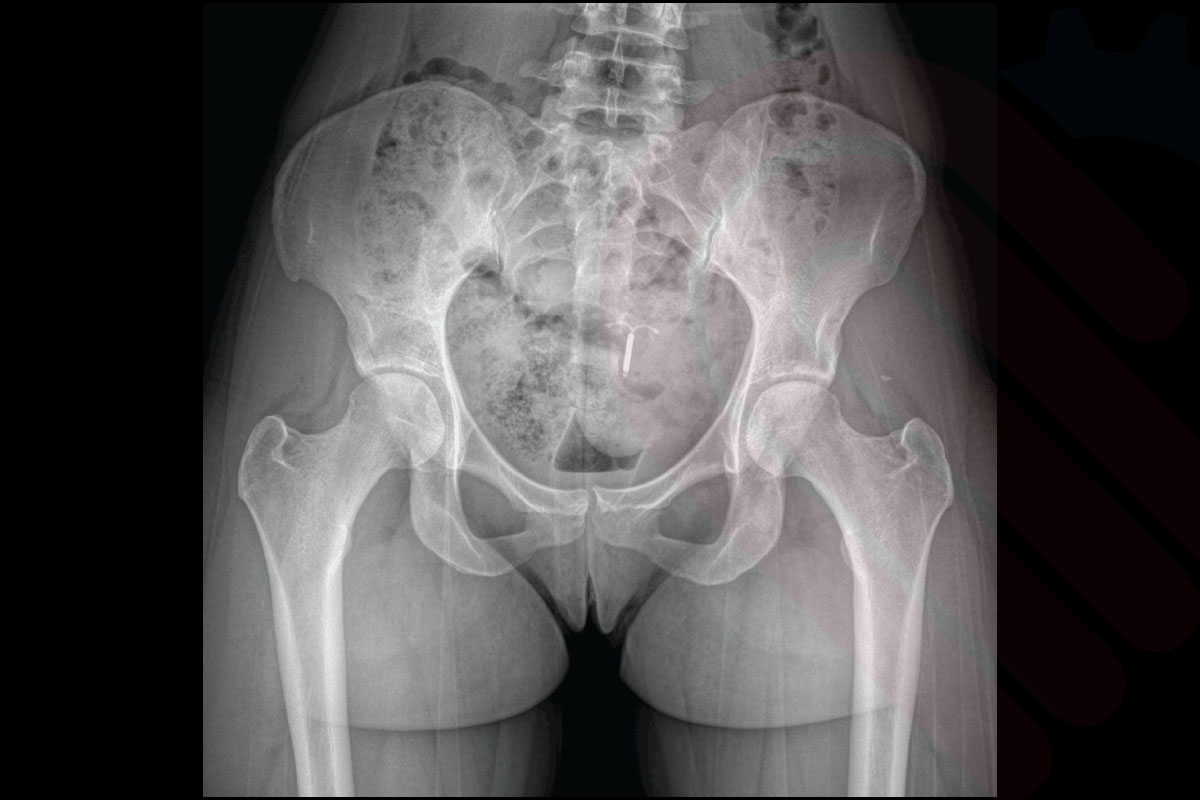

EOSedge®, ortopedi ve kas-iskelet sistemi tanısında yeni bir standart belirleyen, düşük doz radyasyonla yüksek çözünürlüklü biplanar görüntüleme sağlayan gelişmiş bir sistemdir. Skolyoz, kalça-diz deformiteleri, alt ekstremite hizalanma bozuklukları ve travma sonrası değerlendirmelerde; 1:1 oranlı, distorsiyonsuz ve yük taşıyan pozisyonda alınan görüntülerle cerrahlara güvenilir tanı ve cerrahi planlama imkânı sunar.

EOSedge, aynı anda hem önden (AP) hem de yandan (lateral) yüksek çözünürlüklü görüntüler alabilen biplanar görüntüleme teknolojisine sahiptir. Bu sayede, hasta tek bir pozisyonda dururken iki farklı perspektiften tam iskelet görüntüsü elde edilir. Biplanar yapı, anatomik detayların doğru şekilde değerlendirilmesini sağlar ve cerrahi planlamalarda yüksek doğruluk sunar.

Ayrıca, 1:1 oranlı doğrudan görüntüleme özelliği ile çekilen görüntülerde ölçeklendirme hatası ortadan kalkar. Bu, skolyoz ölçümleri, alt ekstremite uzunluk analizleri ve protez planlamalarında kritik öneme sahiptir. Cerrahlar, hastanın gerçek boyutlarına sadık kalınarak elde edilmiş görüntüler üzerinden çalıştığı için, operasyon sonrası beklenmedik uyumsuzluk riskleri en aza iner.

hipEOS, EOSedge sistemi ile elde edilen düşük doz, gerçek boyutlu biplanar görüntüler üzerinden kalça ekleminin 3D analizini ve cerrahi planlamasını yapan gelişmiş bir yazılımdır. Total kalça protezi (THA) ve diğer kalça rekonstrüksiyon cerrahilerinde, asetabular kupa açısı, femoral stem pozisyonu, bacak uzunluğu farkı ve offset gibi kritik parametreleri preoperatif olarak belirlemenize olanak tanır. Yük taşıyan pozisyonda elde edilen görüntüler sayesinde, implant yerleşimi ve pozisyonlaması hastanın doğal biyomekaniğine en uygun şekilde planlanabilir. Klinik veriler, hipEOS planlaması ile gerçekleştirilen operasyonlarda postoperatif bacak uzunluğu eşitliği ve komponent pozisyon doğruluğunda anlamlı iyileşmeler olduğunu göstermektedir*.